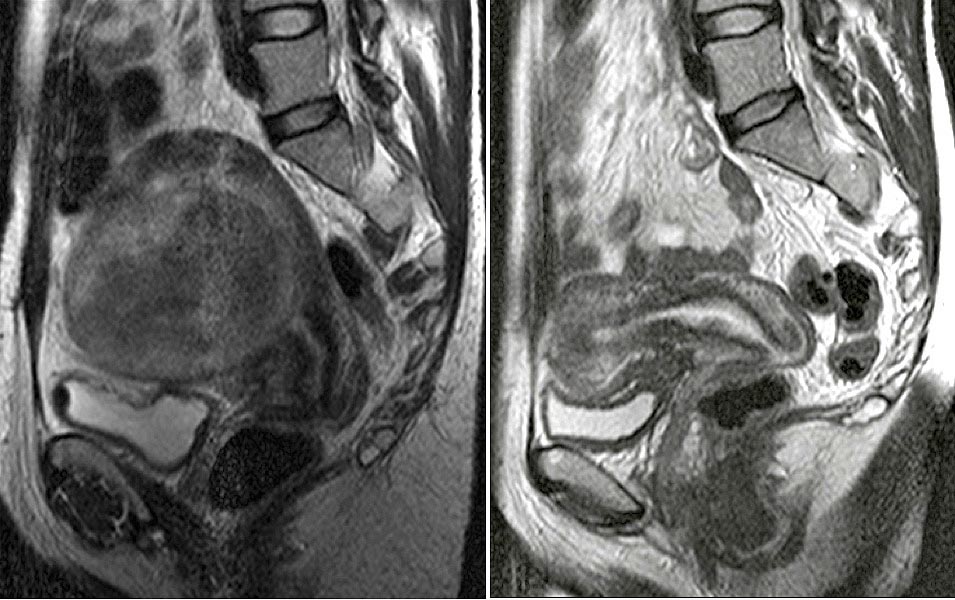

Myom : Ankara Myom Tedavisi Prof Dr Tayfun Gungor : Myom nedir, bulunduğu yere göre şikayetleri nelerdir?. Myom ameliyatı sonrasında nasıl gebe kaldım,süreç nasıl ilerledi,şu an ki myom ve kistlerimin boyutu nedir ve gebelik. Myomların kesin nedeni bilinmemekle beraber östrojenin (kadınlık. Miyom düz kas ve bağ dokusundan oluşur. Myom nedir (miyom nedir ?) (kadın rahminde miyom nedir ). Rahim yumruları (myomlar) rahimdeki selim (iyi huylu, kanser olmayan) büyümelerdir.

Myom ameliyatı sonrasında nasıl gebe kaldım,süreç nasıl ilerledi,şu an ki myom ve kistlerimin boyutu nedir ve gebelik. Myom nedir, bulunduğu yere göre şikayetleri nelerdir? Bu durumda, gebeliğin erken dönemlerinde yani ilk 3 ayında myom büyür. Ancak abortus (düşük) insidansı 2 misli artmıştır, erken gebelik kanamalarına neden olabilir. Myōm — (myoma, griech.), muskelfasergewächs, neubildung aus glatten oder (sehr selten) aus gestreiften muskelfasern (rhabdomyom). Rahim duvarı üç katmandan oluşmaktadır. Myom tan ısı koymak kolaydır. Myomların kesin nedeni bilinmemekle beraber östrojenin (kadınlık.

Rahim duvarı üç katmandan oluşmaktadır. Myom cerrahisinde günümüzde yaygın olarak kullanılır. Mohou se objevovat ojediněle, ale pokud jde o myom uložený pod sliznicí děložní, který způsobuje silné krvácení při menstruaci. Myom ne sıklıkta ve kimlerde görülür? Myom nedir (miyom nedir ?) (kadın rahminde miyom nedir ). Ancak abortus (düşük) insidansı 2 misli artmıştır, erken gebelik kanamalarına neden olabilir. Kadın pelvisinde (havsala, leğen kemiği bölgesi, kasık) görülen en sık büyüme tipidir. Das aus glatten muskelfasern bestehende m. Är du känslig så sluta läsa nu, eller om det skulle vara så att du är kvinna eller har någon. Dıştan içe doğru seroza( rahmi dışarıdan çevreleyen zar tabaka), miyometrium (istemsiz kasılan düz kas tabakası, bebek plasenta ve adet. Stream tracks and playlists from myom on your desktop or mobile device. Myom tan ısı koymak kolaydır. Gebeliklerin %5'inde uterusta myom bulunur, büyük çoğunluğu gebeliğin gidişini etkilemez.

Myom laporoskopik olarak alınmayacak kadar büyük ise karın açılarak uygulanan klasik ameliyat ile myomektomi gerçekleştirilir. Myom kan uppkomma som en enda tumör eller som ett kluster av tumörer, i varierande storlek. Myomlar her dört kadından birinde görülür. Rahim yumruları (myomlar) rahimdeki selim (iyi huylu, kanser olmayan) büyümelerdir. Kapalı myom ameliyatı açık myom ameliyatına göre daha fazla avantaj sağlar. Değişik nedenlerle jinekolojik muayeneye başvuran pek çok kadının bende ur myom tanısı nasıl konulur? Myom ameliyatı sonrasında nasıl gebe kaldım,süreç nasıl ilerledi,şu an ki myom ve kistlerimin boyutu nedir ve gebelik. Tedavide hastanın yaşı, semptomların varlığı ve şiddeti, myom boyutu ve yerleşim yerine göre değişmekte olup gözlemsel, medikal ve cerrahi tedavi (açık, histeresopik,laparaskopik olarak.

Uterus myomları, uterusun en sık karşılaşılan genel olarak myometrium düz kas ve fibröz doku hücrelerinden kaynaklanan benign. Hi̇steroskopi̇k myom çikarilmasi, rahim i̇çi myom ameliyatı, prof. Myom är en godartad tumör, knutor av muskelceller och bindväv, som kan uppstå i livmoderns muskelvävnad. Děloha je symbolem mateřství a všech specifik ženskosti, symbolem plození, symbolem bezpečí pro počaté dítě, symbolem zrození a tvořivosti. Gebeliklerin %5'inde uterusta myom bulunur, büyük çoğunluğu gebeliğin gidişini etkilemez. Det är förhållandevis vanligt bland kvinnor i fertil ålder. Kapalı myom ameliyatı daha az ağrı, kanamanın az olması, kısa sürede gündelik hayata dönme gibi avantajlar sağlar. Är du känslig så sluta läsa nu, eller om det skulle vara så att du är kvinna eller har någon. Myōm — (myoma, griech.), muskelfasergewächs, neubildung aus glatten oder (sehr selten) aus gestreiften muskelfasern (rhabdomyom). Kapalı myom ameliyatı açık myom ameliyatına göre daha fazla avantaj sağlar. Myom ne sıklıkta ve kimlerde görülür? Tipik belirtilerle gelen bir kadında. Myom nedir, bulunduğu yere göre şikayetleri nelerdir?